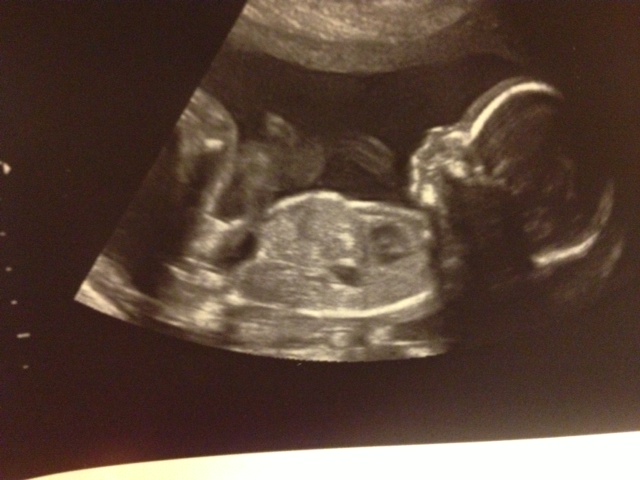

Thanks & they did. Here is the photo...Attachment 12614

I am pretty sure both testicles and a penis are seen in that side shot you posted second, so I think it's a boy. That really doesn't look like a girl in the least. However, it's a side shot, instead of an under the bum shot, so I would want to confirm one more time. But I think I would function under the assumption that its a boy.

You can definitely make out a penis & scrotum in the second pic you posted, but its just a funny angle rather than your typical 'potty' shot. Congrats!!

all boy!